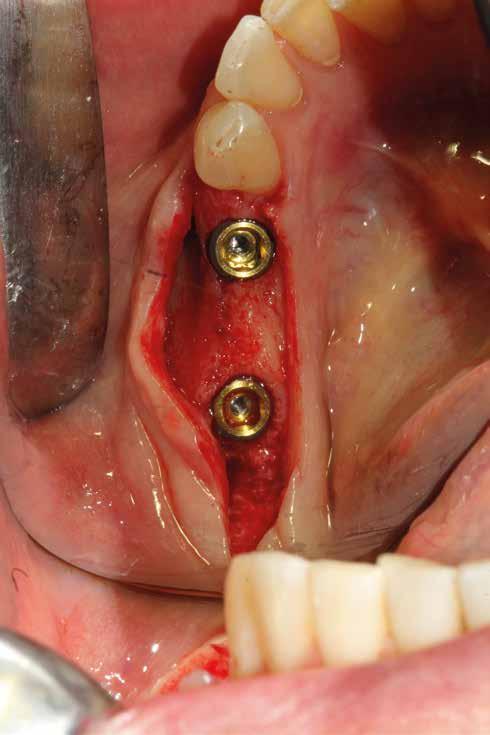

In questo Capitolo saranno prese in considerazioni tre sequenze chirurgiche, che possono essere condotte insieme o separatamente, il cui denominatore comune deve essere la “chirurgia delicata”:

1. Accessi chirurgici (Figg. 1,2)

2. Estrazione dentaria (Figg. 3-6)

3. Preparazione del sito implantare (Figg. 7,8)

Un ridotto scollamento dei tessuti molli riduce edema e dolore post operatorio, mentre la preparazione del sito implantare a bassi giri con irrigazione limita il trauma del tessuto osseo.

Per ottenere una buona guarigione in tempi fisiologici è importante iniziare l’intervento chirurgico nell’ottica del massimo rispetto dei tessuti. Questo obiettivo può essere raggiunto minimizzando l’estensione dell’incisione ed esercitando una divaricazione dei lembi sufficiente a garantire visuale libera al chirurgo. Per la preparazione del sito implantare utilizzare la fresatura a bassi giri garantisce un minor impatto stressante sul tessuto osseo. Per aiutare la riparazione sono fondamentali due fattori: l’impiego degli emocomponenti e una buona tecnica di sutura. Questo percorso consente di ottenere un sigillo di qualità già a 7 giorni dall’intervento.